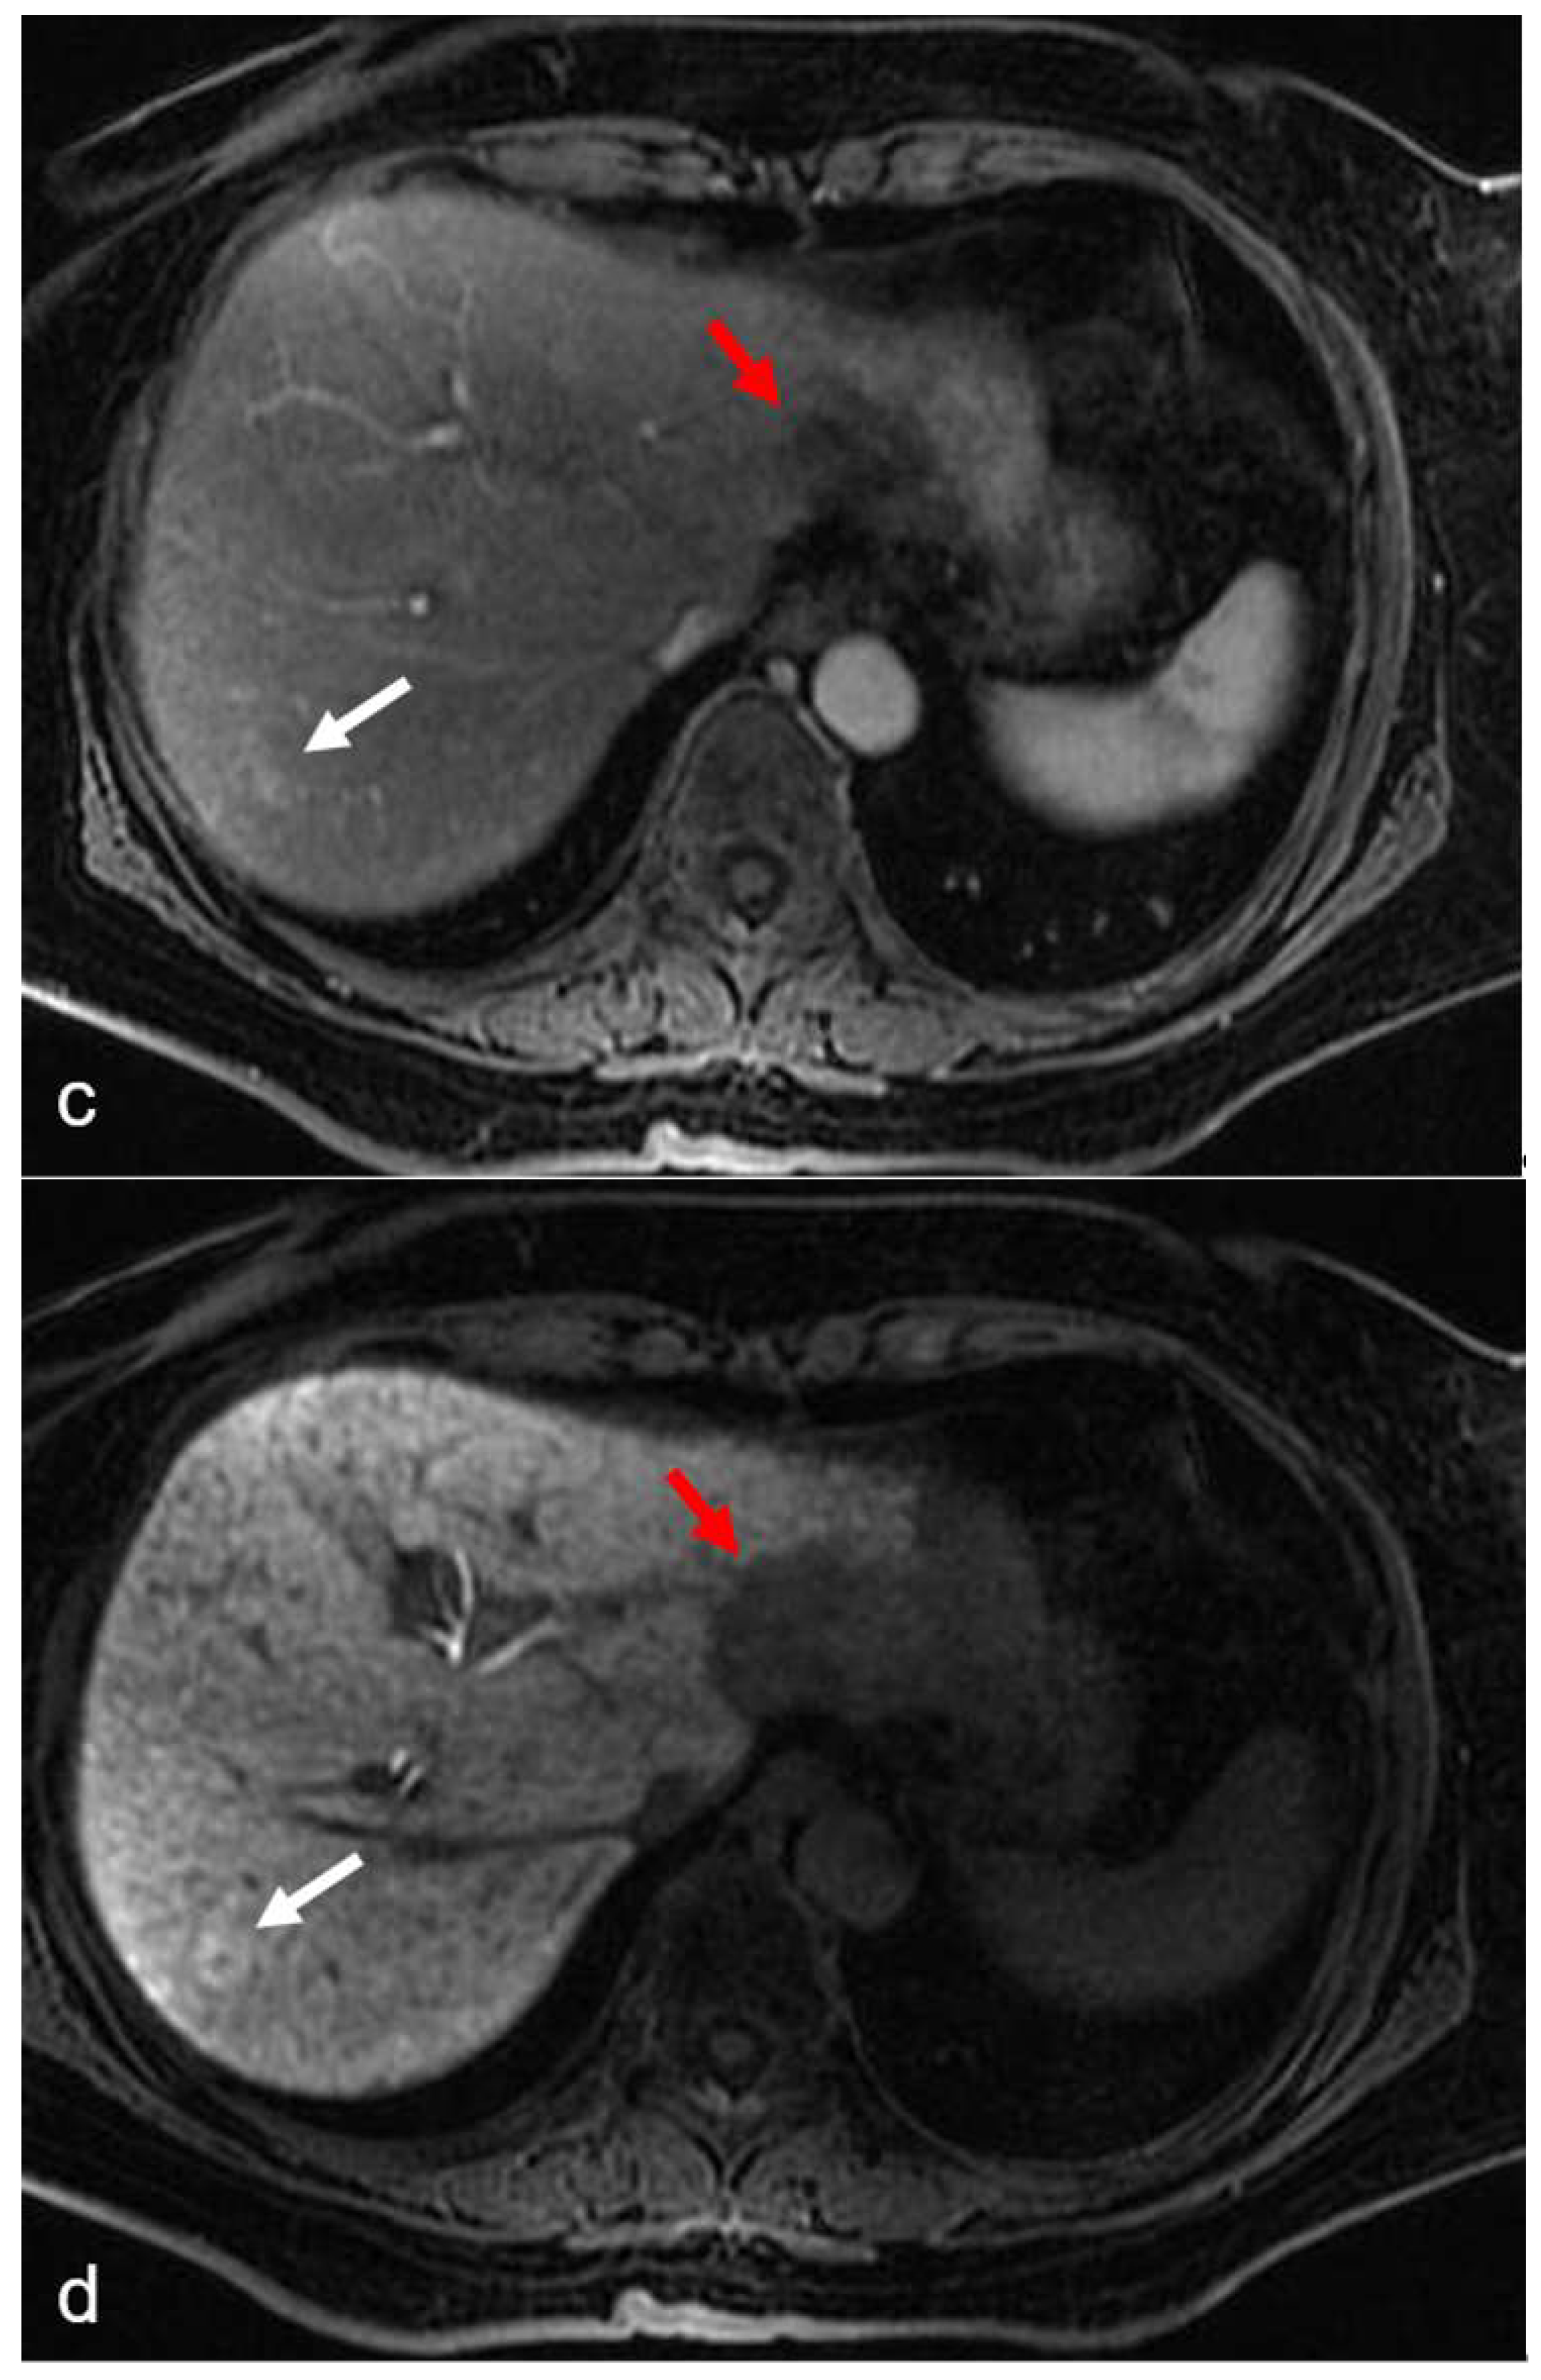

Figure 3.

(a–d) A 55-year-old man with hepatic metastases from rectal cancer undergoing neo-adjuvant chemotherapy with folinic acid, 5-fluorouracil, and oxaliplatin (FOLFOX). After chemotherapy, in the same plane as metastasis of the left lobe (red arrow), a small focal lesion developed in segment 6 (white arrow). The lesion was hyperintense in the T2-weighted image (a) and presented a slight restriction in the DW-MRI image, with b-values of 1000 s/mm2 (b). The arterial phase (c) of the Gd-EOB-DTPA-enhanced MR image demonstrated homogeneous and strong enhancement at the level of the lesion, which presented a doughnut-like enhancement with hyperintense periphery and a hypointense center in the hepatobiliary phase image (d). The findings are consistent with an FNH-like lesion. In the hepatobiliary phase image (d), the patchy heterogeneity of the surrounding hepatic parenchyma, with reticular enhancement and scattering of hypodense areas, is also appreciably suggestive of SOS.

Shin et al. [36] reported that the presence of hepatic reticular hypointensity in the hepatobiliary (HB) phase of gadoxetic acid-enhanced MRI was highly specific for the diagnosis of SOS (Figure 3).

In MR imaging, FNH-like lesions usually show strong enhancement in the arterial phase and isoattenuation to the surrounding liver parenchyma during the portal venous and delayed phases [4]. A central scar is present in fewer than 50% of cases [47]. The specificity for the diagnosis of these benign lesions with non-invasive imaging has improved with the use of hepatobiliary MR contrast agents [4,48,49,50]. After the injection of gadoxetic acid and gadobenate dimeglumine, FNH-like lesions are usually iso- to hyperintense during the MRI HB phase because of a similar or stronger OATP1B3 expression than in the background liver [49]. In addition, a ring of enhancement may be present in up to 50% of cases and is characterized by doughnut-like enhancement (hyperintense periphery and a hypointense center) [47] (Figure 3). Unlike metastases, which appear as hypointense lesions during the HB phase of MRI, the isointensity or hyperintensity of FNH-like lesions is highly specific [34].